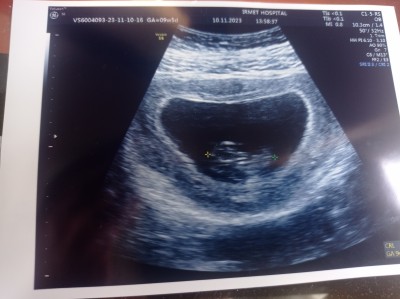

Kızlar cinsiyet tahmininiz varmi acaba

10 haftalik olduk cinsiyetimize bakarmisini

Çok bulanık canım h hafta küçük

Haftası daha küçük keseye göre yorum yapım bari bence erkek olur hayırlısi olsun